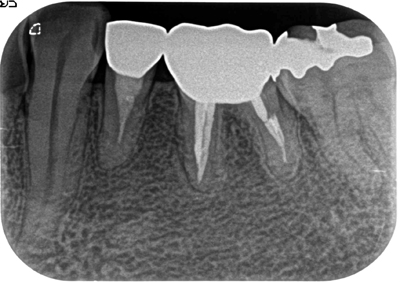

症例1【30代女性】右上7番根尖相当部に大きな病巣がみられ、副鼻腔の粘膜にも波及し、肥厚している。15ヶ月後、病巣はほぼ消失し、骨が再生、副鼻腔粘膜の肥厚も消失。

治療前

治療後(15ヶ月後)